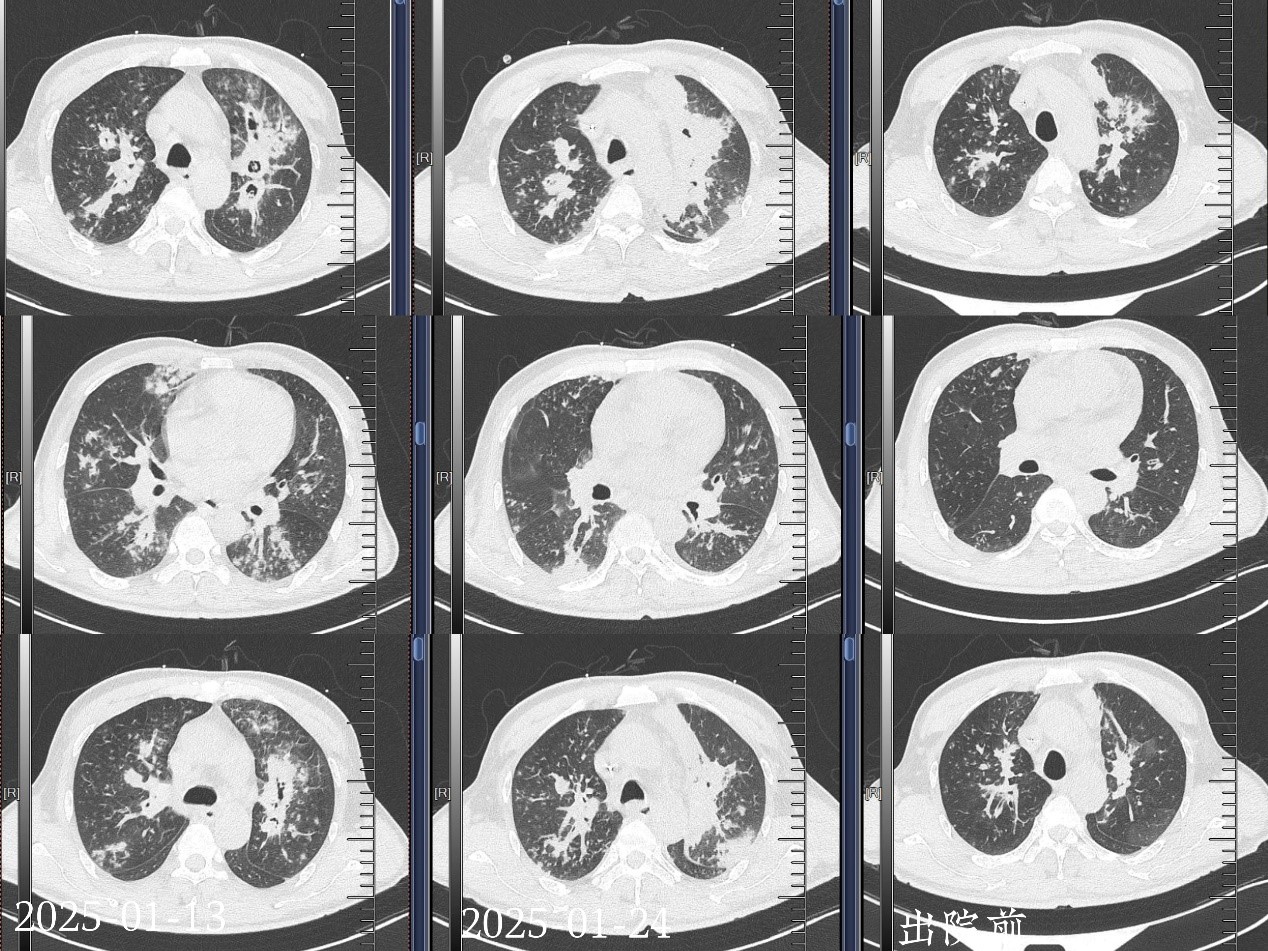

60岁的陈先生,因咳嗽、胸闷一周就诊。看似普通的症状背后,却隐藏着重重危机,患者长期吸烟、饮酒,且患有高血压和2型糖尿病,这些不良生活习惯与基础疾病悄然为病情恶化埋下危险的种子。患者在外院就医时起初诊断为细菌性肺炎,但常规抗感染治疗却让病情急转直下,胸部CT显示双肺斑片状阴影,白细胞计数飙升至19.38×10^9/LCRP高达282.19mg/L,糖化血红蛋白更是达到13.0%,如此失控的血糖水平让他本就脆弱的免疫系统彻底“瘫痪”。更为棘手的是,这场疾病已不再局限于肺部,牵连至多个系统,肝脏、肾脏等重要脏器的功能也受到不同程度的损害,陈先生的身体状况岌岌可危,逐渐出现呼吸衰竭,一场与死神的赛跑迫在眉睫。

呼吸内镜下治疗在这场治疗战役中发挥了举足轻重的作用。团队凭借精湛的技术,先后四次运用呼吸内镜,精准地将两性霉素喷洒到感染病灶。每次操作都经过严密的规划和细致的准备,医生们在操作过程中全神贯注,凭借丰富的经验和精准的手法,确保药物能够均匀且准确地覆盖在病变部位,直接对真菌进行“打击”,有效遏制了病情的恶化,连续多次的气管镜操作,既是治疗手段,更是动态评估病情的“窗口”。通过每次气管镜下呈现的坏死组织范围、脓苔黏附程度以及有无肉芽增生等情况,实时、动态地调整治疗药物,做到治疗方案的精准优化。同时,团队成员迅速全面地开展了一系列综合治疗措施,多管齐下为患者的康复保驾护航。给予抗病毒,输注白蛋白、丙种球蛋白、血浆支持治疗,辅以止咳、雾化、化痰、降糖、保肝、补钾、高流量氧疗等综合治疗,全方位保障患者的身体机能。

通过积极治疗一月后,患者终于能自主下床行走,回想起这段惊心动魄的经历,陈先生眼眶泛红,满是感激,他激动地说道:“村里的人都以为我已经离开了,是你们硬是把我从死神手里抢了回来,给了我第二次生命啊!"37号患者终于康复出院,将一面锦旗郑重交到蒋军红主任手中,那不仅仅是对蒋军红主任团队医术的高度赞誉,更是一段生死营救历程的见证,承载着患者重获新生的喜悦与对医护人员深深的感恩之情。